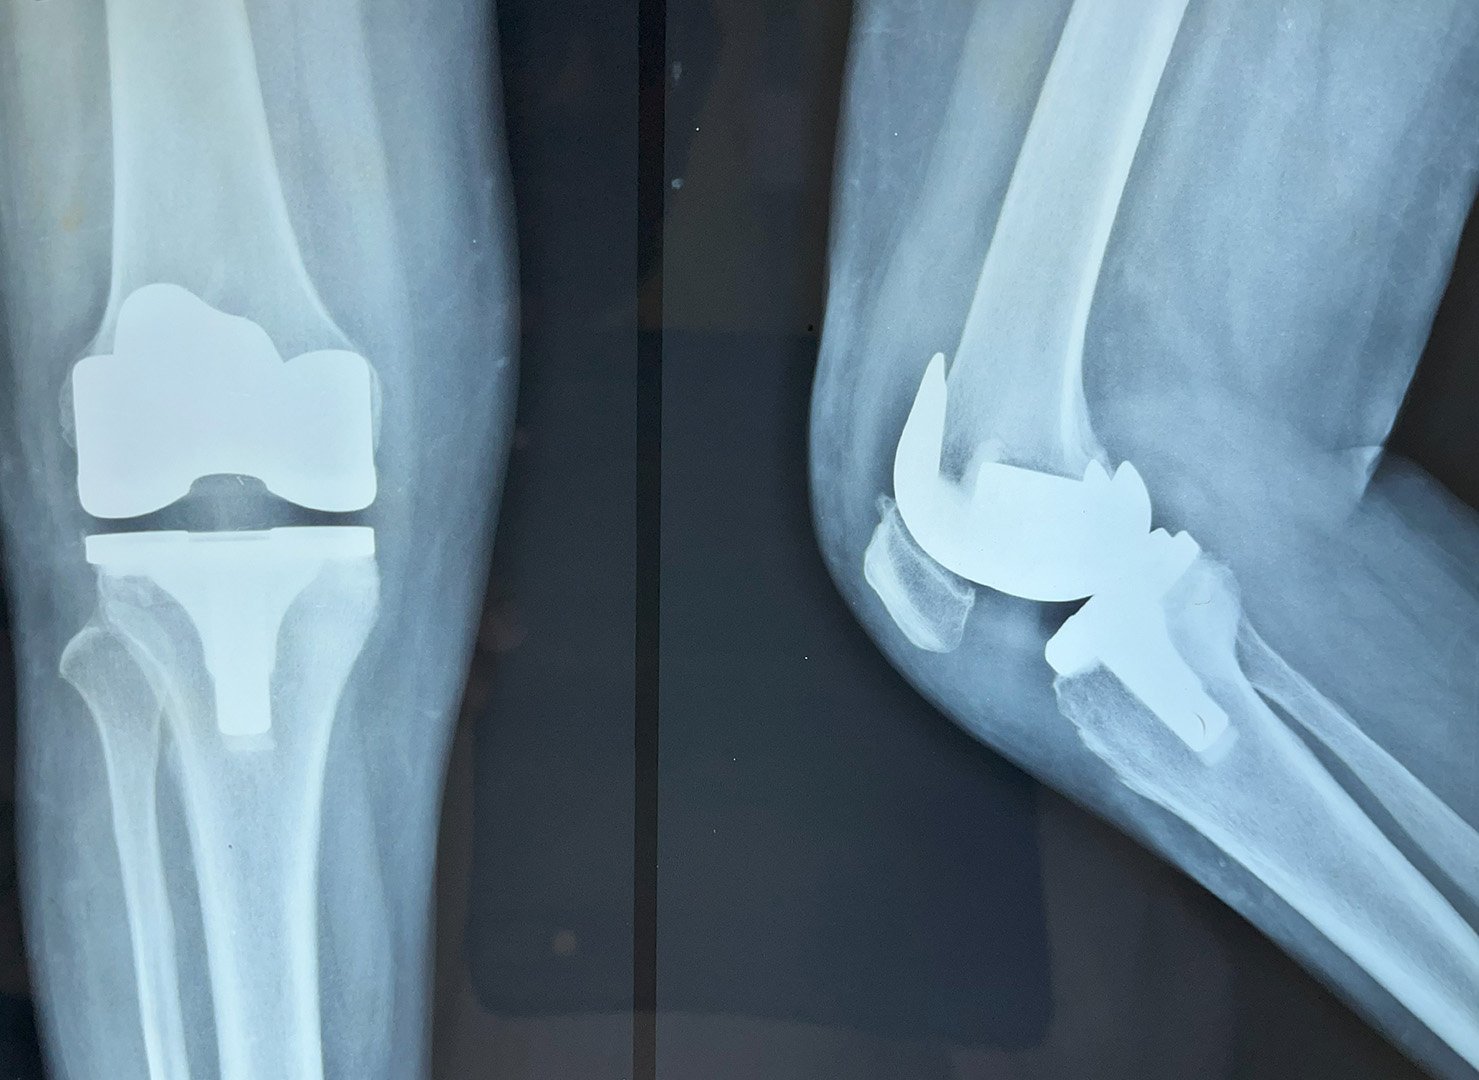

Post-Op Follow Up